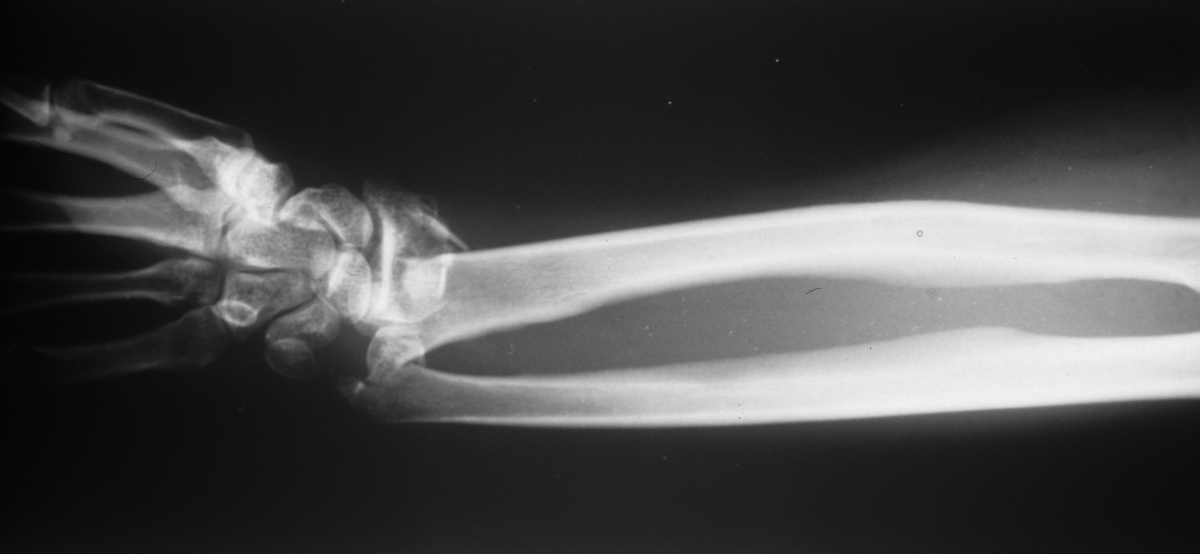

| Ulnar styloid position on a

forearm AP radiograph demonstrates the degree of rotation |

| Uneventful healing. Final

supination was 45 degrees. |